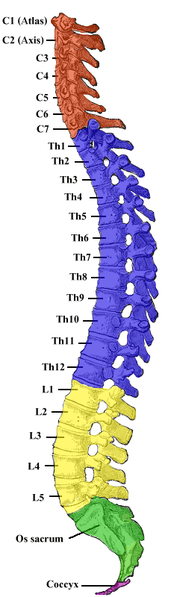

- The Spinal Cord

Spinal cord

The spinal cord plays a critical role in transferring stress response neural impulses from the brain to the rest of the body. In addition to the neuroendocrine blood hormone signaling system initiated by the hypothalamus, the spinal cord communicates with the rest of the body by innervating the peripheral nervous system. Certain nerves that belong to the sympathetic branch of the central nervous system exit the spinal cord and stimulate peripheral nerves, which in turn engage the body's major organs and muscles in a fight-or-flight manner.